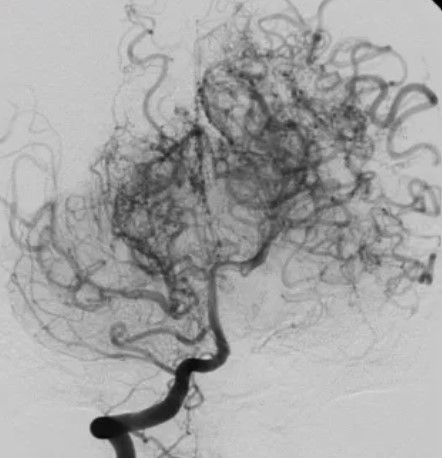

모야모야병(Moyamoya disease)은 뇌로 가는 주요 동맥이 점차 좁아지면서 뇌에 혈류가 부족해지고, 그로 인해 주변에서 가느다란 새로운 혈관들이 생성되는 희귀한 만성 뇌혈관 질환입니다. 이 새로운 혈관들이 연기처럼 보인다고 하여 일본어 '모야모야(もやもや)'에서 이름이 붙여졌습니다.

모야모야병의 진단은 뇌혈관의 협착 정도와 대체 혈관 형성 여부를 파악하는 것이 핵심입니다. 주로 다음과 같은 방법이 사용됩니다:

- MRA (뇌혈관 자기공명영상): 비침습적으로 혈관의 협착과 모야모야혈관을 시각적으로 확인합니다.

- CTA (컴퓨터 단층촬영 혈관조영술): CT 기반 혈관 조영으로 빠르게 뇌혈관 상태를 확인합니다.

- DSA (디지털 뇌혈관 조영술): 카테터로 조영제를 주입해 혈관을 가장 정확하게 확인하는 방법으로, 수술 전 꼭 필요합니다.